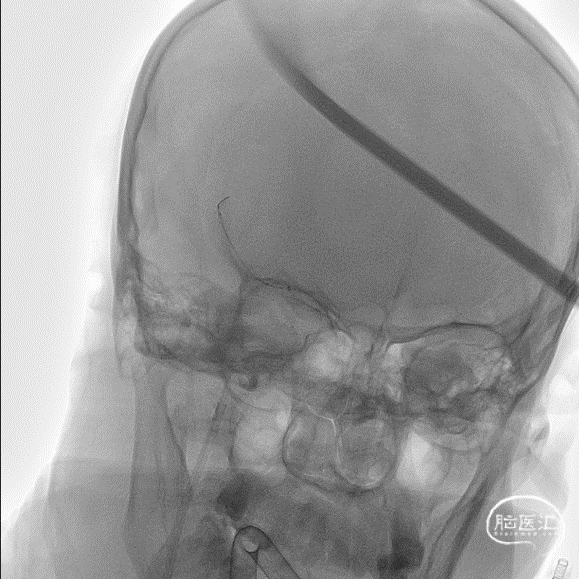

术前造影提示右侧大脑中动脉下干闭塞。

使用8F导引导管在6F 125cm Tethys®中间导引导管同轴下超选至右侧颈内动脉建立通路,造影可见右侧大脑中动脉M1下干闭塞。

Tethys®中间导引导管到达大脑中动脉血栓部位,边抽边撤Tethys®中间导引导管,未见血栓;Tethys®中间导引导管再次到位大脑中动脉,微导丝微导管通过闭塞段,微导管造影证实在真腔。

释放3*25mm Syphonet®取栓支架,停留5分钟后撤出Syphonet®取栓支架并保持负压抽吸,第一次复查造影血流未通。

再次重复上述操作,释放Syphonet®取栓支架并停留5分钟后撤出取栓支架并保持负压抽吸,再次复查造影右侧大脑中动脉下干血流恢复,mTICI血流3级。